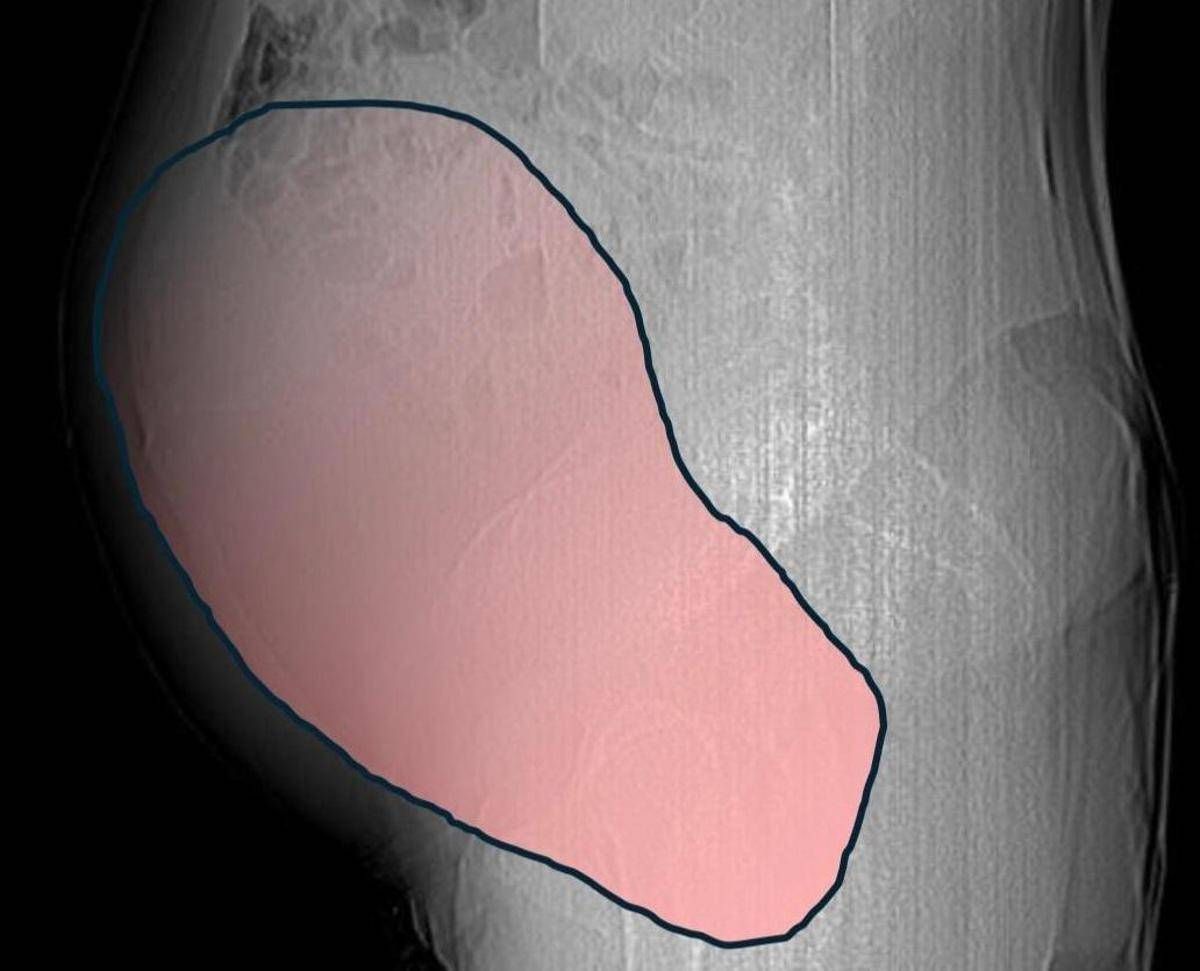

(Adnkronos) – Una donna di 69 anni ha scoperto di essere affetta da un tumore ovarico di dimensioni eccezionali, paragonabili a quelle di una gravidanza gemellare a termine, solo quando il suo organismo ha improvvisamente iniziato a cedere. Per mesi la gigantesca cisti ovarica, con un diametro di circa 28 centimetri, è rimasta nascosta, senza dare segnali evidenti. La paziente non si era accorta di nulla. L’allarme è scattato quando la massa, associata alla presenza di una seconda neoplasia intestinale, ha iniziato a comprimere il colon, provocando sintomi acuti ed improvvisi fino ad una grave difficoltà intestinale non più ignorabile. A riferire la storia è l’ospedale Sant’Anna di Torino.

Il caso risale a metà dicembre quando la donna arriva all’attenzione dei sanitari e a prendere in carico il caso è la Chirurgia Ginecologica Mininvasiva dell’ospedale Sant’Anna diretta dal dottor Paolo Petruzzelli. I tempi sono strettissimi, con le festività natalizie alle porte, ma la risposta è immediata: in pochi giorni si definisce l’inquadramento diagnostico, stadiazione e percorso terapeutico. Il 23 dicembre, a poche ore dalla vigilia di Natale, la paziente entra in sala operatoria. L’intervento dura circa sei ore. ”Durante l’intervento emerge tutta la gravità della situazione – spiegano dall’ospedale – La gigantesca neoplasia ovarica viene asportata: pesa circa 6 chilogrammi, con un volume paragonabile a quello di una gravidanza gemellare a termine. Ma non è l’unica minaccia. I sintomi più pericolosi sono legati alla sofferenza intestinale, che richiede un intervento immediato e coordinato di più specialisti”.